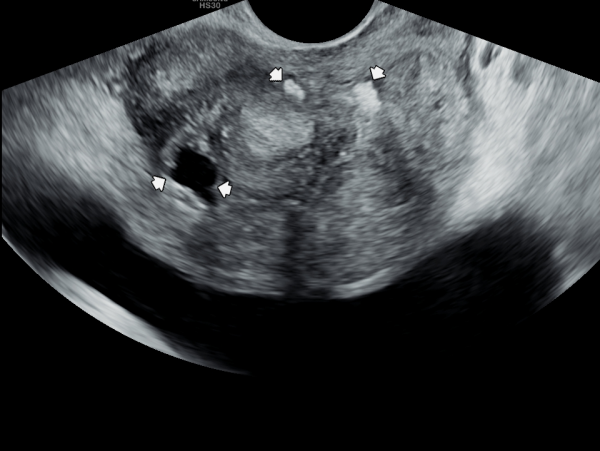

10년전부터 배뇨장애와 빈뇨로 비뇨기과에서 약을 복용중 2년전부터 급박뇨와 요실금이 심해져 투약을 했으나 증상의 호전이 없다고 내원당일 검사한 경직장 전립선 초음파 검사상 전립선 비대와 전립선의 낭종과

사정관주위의 결석이 관찰되는 경직장 전립선 초음파 사진입니다.

This is a transrectal prostate ultrasound image taken on the day of the visit. The patient had been taking medication for urinary difficulties and frequent urination for over 10 years at a urology clinic. However, since two years ago, symptoms of urgency and urinary incontinence worsened despite continued medication. The ultrasound shows prostate enlargement, cysts within the prostate, and calcifications around the ejaculatory ducts.